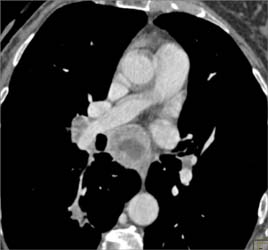

Occlusion of Left Lower Lobe Bronchus